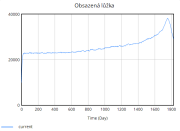

| 22:35, 15 June 2025 | 1 ObsazenáLůžka.png (file) |  |

12 KB | Kozo01 | 1 | |